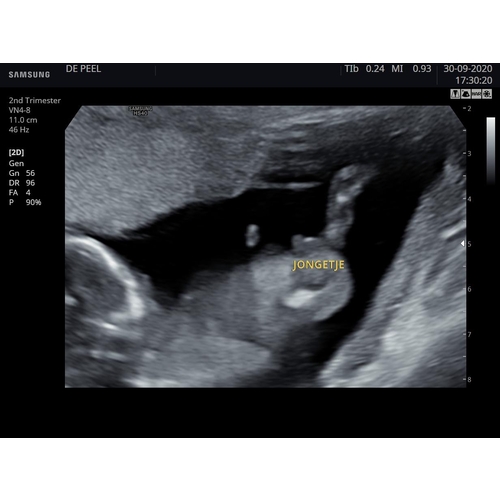

Wij kregen deze foto mee... kan er zelf niet veel van maken, maar de echoscopiste was vrij zeker van haar zaak... we zullen bij 20 weken wel horen of ze gelijk heeft😅

Ziet er zeker uit als een jongen haha. Je ziet duidelijk een piemel en ballen